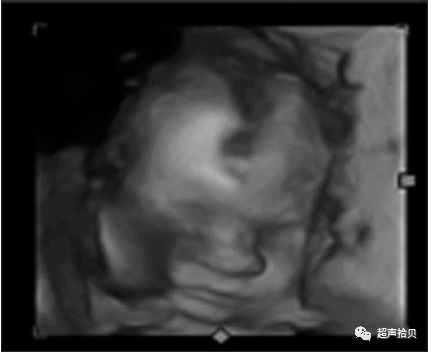

图3胎儿在妊娠25周时从表面到颅骨的三维图像。 A和B,胎儿的表面部分和面部图像。 C和D,胎儿脑部更深的三维切片。 E和F,三维切片显示胎儿脑中的蛛网膜囊肿(箭头)